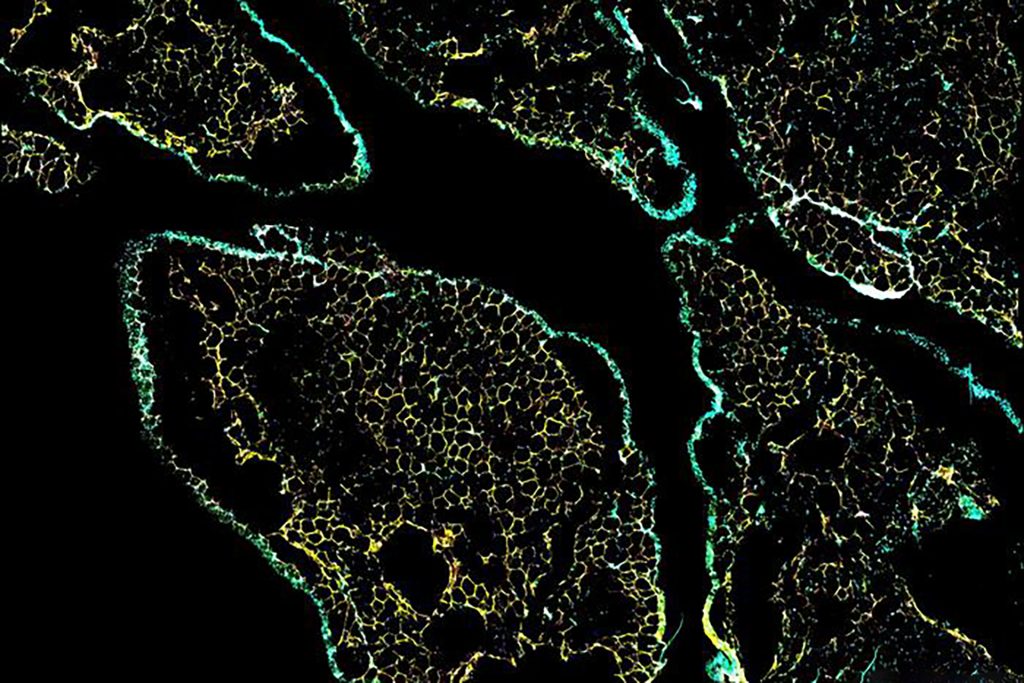

حددت هذه الطريقة مجموعة من الخلايا الموجودة في الأنسجة الدهنية الثربية، والتي قد تكون المفتاح لتفسير خصائصها غير العادية. هذه الخلايا، التي تسمى الخلايا الظهارية المتوسطة (mesothelial cells)، تبطن بشكل عام بعض تجاويف الجسم الداخلية كطبقة واقية.

ومن بين هذه الخلايا الظهارية المتوسطة، انتقل بعضها بشكل غريب إلى ما يشبه الخلايا الوسيطة (mesenchymal cells)، والتي يمكن أن تتطور إلى مجموعة متنوعة من أنواع الخلايا، بما في ذلك الخلايا الشحمية (adipocytes). وقد يكون هذا الانتقال بين الحالات الخلوية آلية رئيسية تمارس من خلالها هذه الخلايا تأثيرها على القدرة الدهنية للأنسجة الدهنية الثربية.